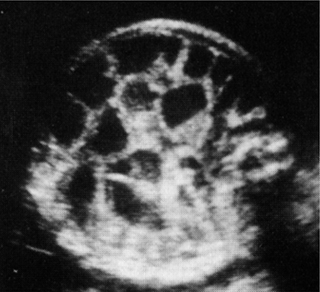

Επιμήκεις και εγκάρσιες τομές μπορούν να χρησιμοποιηθούν για τη μελέτη των νεφρών

(εικόνα 1).

| Εικόνα 1. Φυσιολογική απεικόνιση των νεφρών. | Εικόνα 2. Φυσιολογική